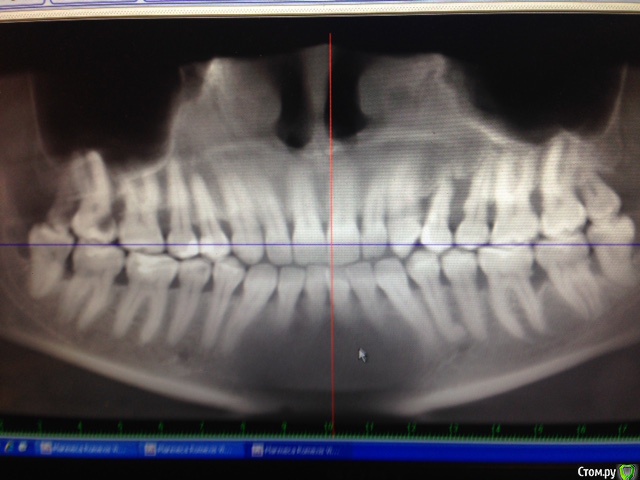

Hellae Опубликовано 17 января, 2016 Поделиться Опубликовано 17 января, 2016 Просьба откликнуться специалистов что делать в моей ситуации. У меня уже год шатается 4 зуб верхней левой челюсти. Длительное время постоянно кровил. Удалять сказали еще в феврале 2015, но я все никак не решалась т.к. вместе с ним требуется удаление еще и 5-го зуба рядом с ним. Плюс ко всему это связано с генерализованным парадонтитом(так мне сказали) на фоне которого и расшатался 4-й зуб. Сейчас имплантолог сказал надо удалить 2 зуба (4 и 5) подсадить костную ткань и ждать когда она приживется, потом ставить импланты, а пока кость нарастает сделать лоскутные операции.Снимки у мня только КТ февраль 2015 я сфотографировала панораму и прицельный двух зубов может можно как то по ним увидеть. Ссылка на комментарий